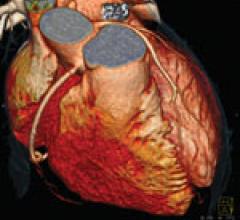

Coronary computed tomography angiography (CCTA) is a noninvasive tool that can be used for identifying myocardial…

Feature | Dave Fornell

There are currently three major trends in cardiovascular computed tomography (CT) technology — lowering radiation dose…